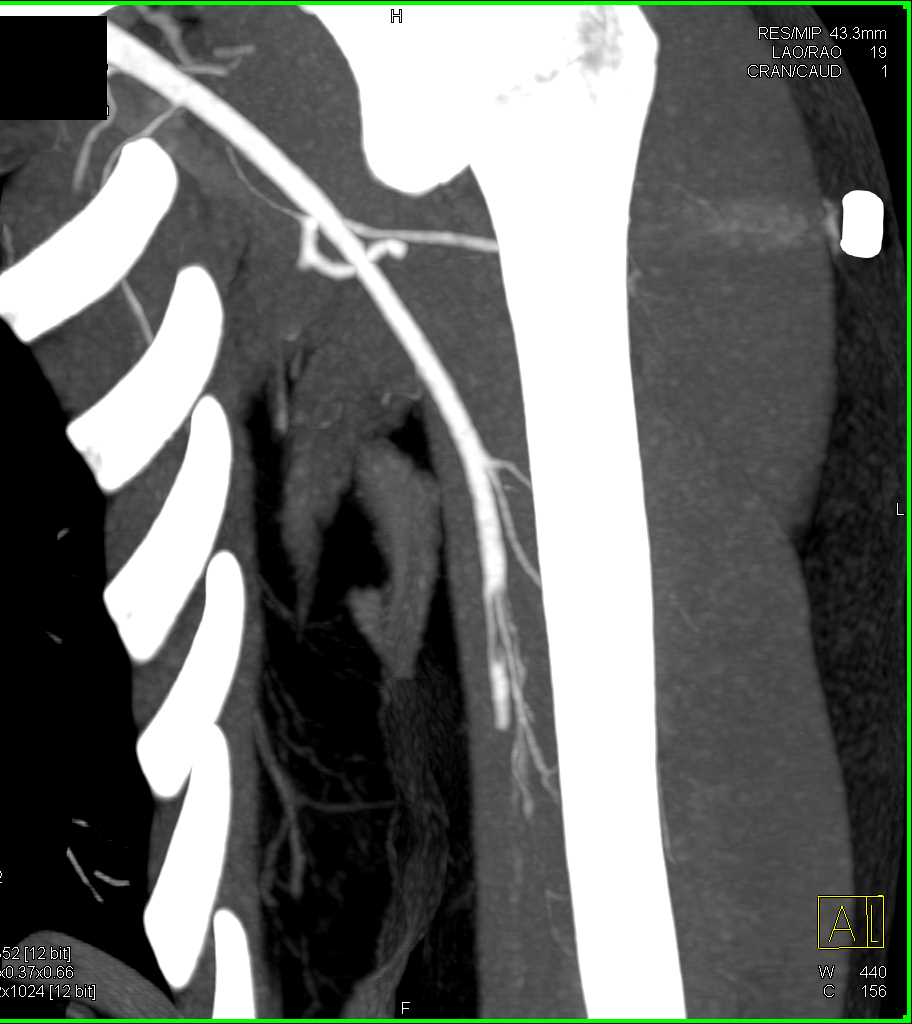

Brachial Artery Occlusion